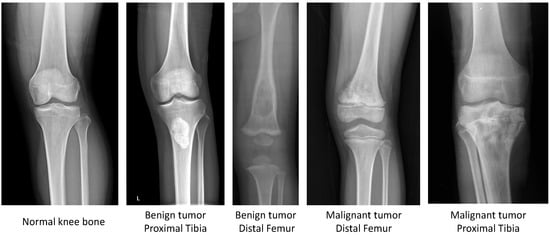

2.1. CNUH Dataset and Challenges

| Knee Region | Benign Tumor | Malignant Tumor | Normal |

|---|---|---|---|

| Distal femur | 598 | 89 | - |

| Proximal tibia | 463 | 45 | - |

| Total | 1061 | 134 | 381 |